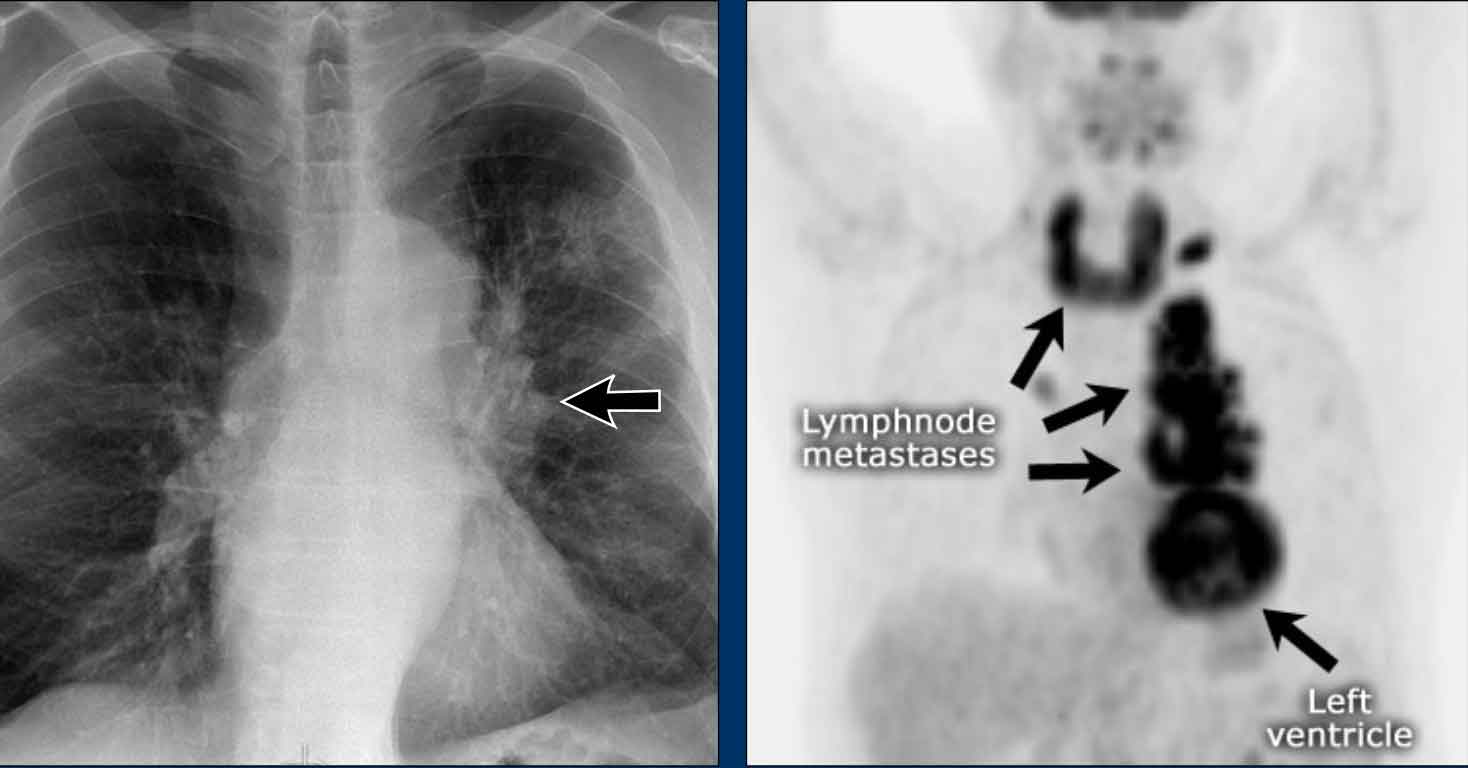

AP window mass - case 2

Imaging

Continue with the PET-CT...

PET-CT

• PET-CT more clearly defines the extent of nodal metastases

• Final diagnosis: Small cell lung carcinoma